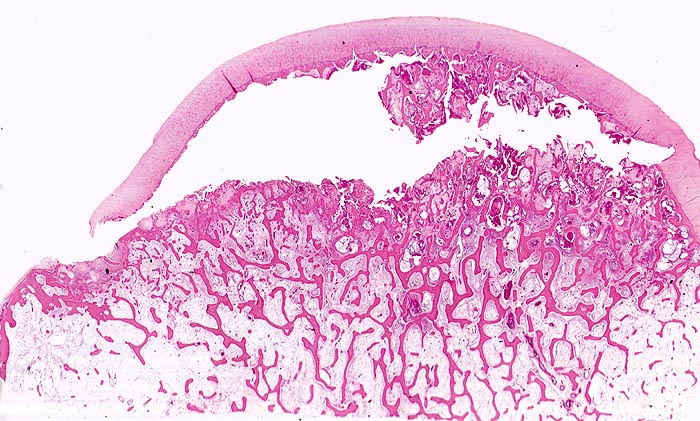

aseptische Femurkopfnekrose

Typische flächenhafte Ablösung des Gelenkknorpels zwischen subchondraler Knochenlamelle und angrenzender nekrotischer Spongiosa. Der Gelenkknorpel ist gut erhalten.

Sekundäre ischämische Knochennekrosen bei Arthrose sind im Gegensatz zur spontanen idiopathischen Knochennekrose des Erwachsenen keilförmig und weniger flächenhaft. Sie entstehen an Stellen des von Knorpel entblössten Hüftkopfes. Bei der aseptischen Knochennekrose ist dagegen der Gelenkknorpel nicht zerstört, sondern lediglich von der nekrotischen Unterlage abgehoben.